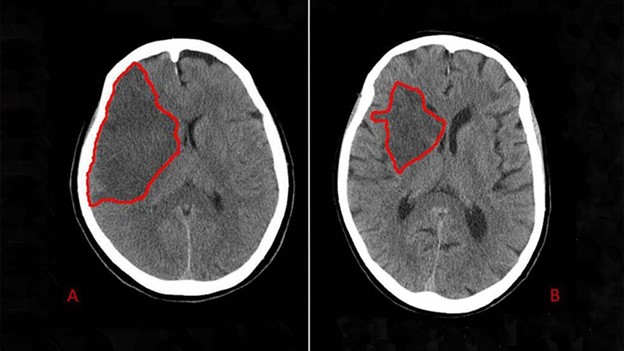

In about 80% of strokes, the interruption to the blood flow is caused by a blood clot. This is called an ischemic stroke. In the other 20% of strokes, it is due to a damaged blood vessel. This is called a haemorrhagic stroke. The symptoms of a haemorrhagic bleed are more severe and can be fatal.